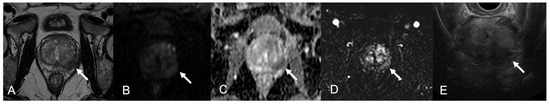

| 1 | 62 | 10 | 0.19 | 54 | PZ; TZ | 4; 5 | 4; 3 | +; + | 4; 5 | BCG-GP |

| 2 | 72 | 7.96 | 0.08 | 95 | PZ | 4 | 4 | + | 4 | BCG-GP |

| 1 | PZpm mid-left; TZa mid-base right | 2-cm hypointense PZ nodule; 1.5-cm marker hypointense irregular TZ lesion | Isointense nodule; Slightly hyperintense | Marked low ADC value; Low ADC value | Peripheral rim enhancement and avascular core; Inhomogeneous, early and prolonged hyperenhancement | 4; 5 |

| 2 | PZpl mid-left | 2.5-cm hypointense nodule, capsular bulging | Hyperintense | Low ADC value | Thick peripheral rim enhancement, avascular core | 4 |